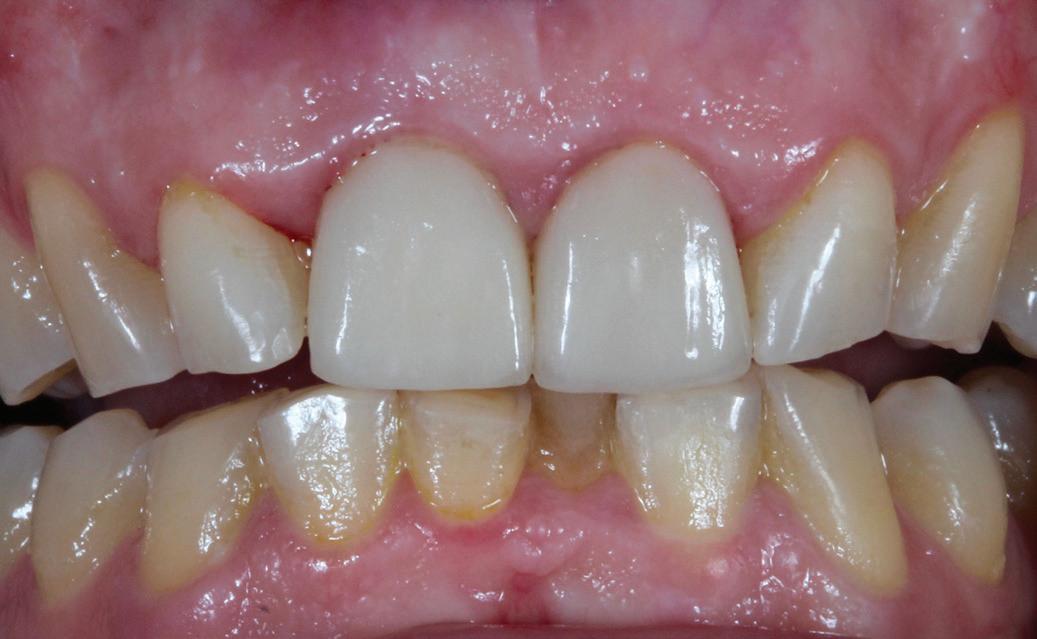

Posibilitatea ca nuanța gri să transpară prin gingie este un posibil dezavantaj al implanturilor de titan. În schimb, datorită culorii albe a dioxidului de zirconiu, această problemă estetică poate fi evitată prin

utilizarea implanturilor ceramice. Desigur, obținerea unei estetici excelente cu implanturile de titan este posibilă în mod curent. Cu toate acestea, o condiție prealabilă pentru un astfel de rezultat este prezența unei mucoase periimplantare cu o grosime de cel puțin 2 mm, care poate împiedica transparența cenușie a titanului. În lipsa acestei grosimi, mucoasa poate fi dublată de o grefă de țesut conjunctiv (recoltată de obicei din palat), necesitând însă o procedură chirurgicală adițională și, prin urmare, o povară suplimentară pentru pacient. Utilizarea bonturilor implantare integral ceramice este o soluție alternativă, dar microdeplasările bontului dur de dioxid de zirconiu pe implantul de titan mai moale pot duce la abraziune și chiar la distrugerea conexiunii implant-bont.

Totuși, ca și în cazul implanturilor de titan, în rare cazuri, și la cele ceramice poate apărea o recesie nedorită cu expunerea umărului implantar. Cu toate acestea, din punct de vedere estetic, această recesie a gingiei inflamate este posibil să fie mult mai bine tolerată de către pacienții preocupați de marginile întunecate ale implanturilor de titan (fig. 2).

1. Implanturi din titan (stânga) și zirconiu (dreapta). 2. Recesii la implanturile ceramice (stânga) și din titan (dreapta). 3. Țesut moale cu implant din zirconia, lipsit de inflamație.